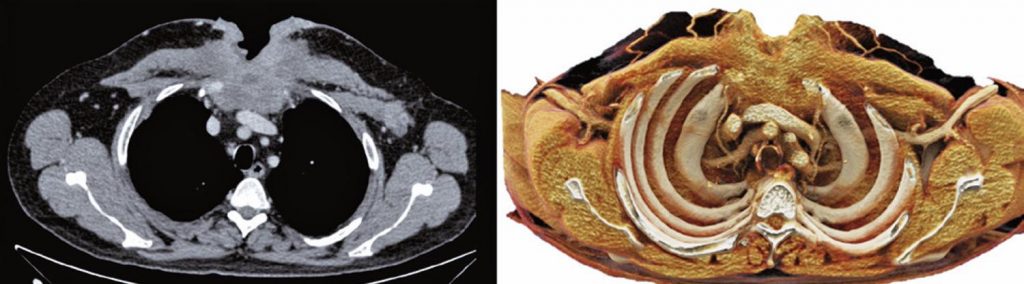

Cinematic rendering for three-dimensional reconstructions of the chest wall: a new reality

Computed tomography with multiple detectors and the advancement of processors improved rendered images and three-dimensional reconstructions in clinical practice. Traditional axial slices form non-intuitive images because they are seen in only one plane. The three-dimensional reconstructions can show structures details and diseases with complex anatomy in different perspectives. Cinematic rendering is a newly three-dimensional reconstruction technique, already approved for clinical use, which can produce realistic images from traditional computed tomography data. The algorithm used is based on light trajectory methods and the global lighting model, which simulate thousands of images from all possible directions. Thus, the technique shapes the physical propagation of light and generates a realistic three-dimensional image with depth, shadows and more anatomic details. It is a multidimensional rendering acquired through complex lighting effects. The aim of this article was to show the advance of three-dimensional technology with the cinematic rendering in images exams of the thoracic wall.